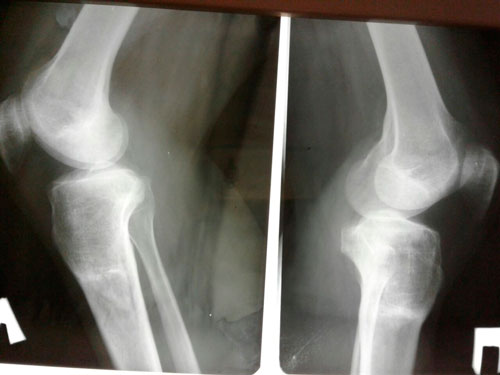

Рентген спустя 3 месяца с момента снятия аппаратов.

Всё отлично! Носите красоту на здоровье! 094f316296.gif

IMG-20171026-WA0002.jpg

IMG-20171026-WA0003.jpg